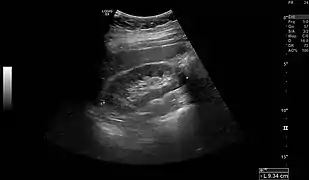

- Normal adult right kidney as seen on abdominal ultrasound with a pole to pole measurement of 9.34 cm.

Renal ultrasonography is essential in the diagnosis and management of kidney-related diseases.[44] Other modalities, such as CT and MRI, should always be considered as supplementary imaging modalities in the assessment of renal disease.[44]